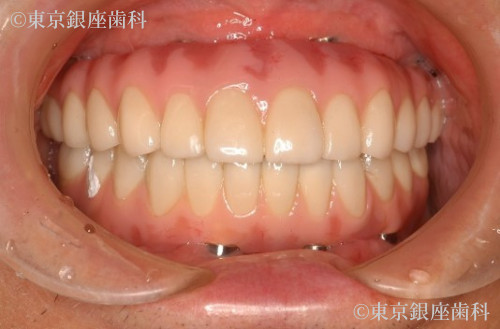

After

ブレードインプラントが下顎管に近接しているので、インプラント除去による下顎の知覚麻痺が生じるリスクを術前のCTの分析で診査し、リスクを避けました。また骨造成は行わず、既存骨(ご本人様の骨)イへのンプラント埋入を行いました。上顎は5本のインプラント、下顎は4本のインプラントを支えとした、上下顎への全顎的な人工歯を装着することで口腔機能の回復が得られた症例となりました。患者様にとても満足の得られることができた症例です